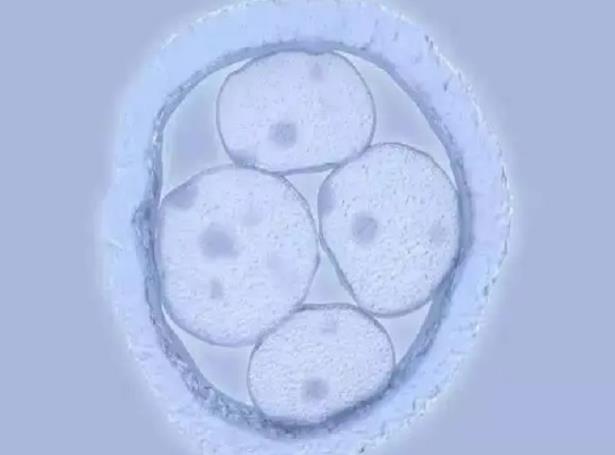

因為老公精子質量不是很好,就去醫院做了二代試管,在周三的時候去醫院移植了兩枚二級胚胎,剛開始沒有異常情況出現,就是感覺腰有點酸痛,不過昨天晚上上廁所的時候,發現內褲上有褐色分泌物印記,因為只有幾滴,就沒有在意,但是今天早上起來,發現內褲上有一小灘分泌物,在網上搜索了一下,說有可能是胚胎移植失敗排出來了,但我覺得不是很像,所以想問一下胚胎排出后是什么樣的呢?知曉自己是否排卵其實有很多的辦法,其中大家用的最多的就是排卵試紙了,其實除了排卵試紙,還有計算排卵日期、基礎溫度測量和觀察宮頸粘液等四種辦法來判斷,所以我們如果掌握這四種辦法的話,就能夠輕輕松松的知曉自己的排卵規律了,更重要的是就能夠更好的準備備孕。內蒙古試管嬰兒醫院排名哪家好,2023內蒙古中醫藥研究所試管成功率預估